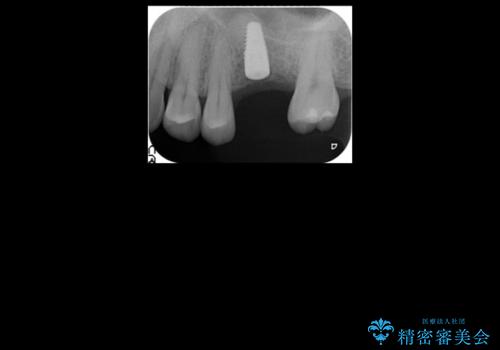

インプラントの向かい合わせの歯や隣の歯の虫歯治療も併せて行なっています。

同時期に治療することで咬み合わせの調整がしやすく、また、適合の良いものを作成できるメリットがあります。

左上6:インプラント(ストローマン)20万円、カスタムアバットメント10万円、スクリューリテイン仮歯2万円、ジルコニアクラウン10万円、ソケットリフト10万円、マイナーGBR 5万円、静脈麻酔(麻酔認定医)5万円